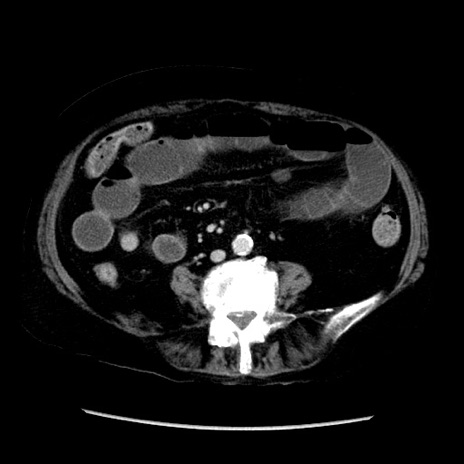

症例14(横断像)

【症例】 90歳代女性

【主訴】 腹痛・嘔吐

【現病歴】今朝から左側腹部痛を認めた。 経過観察していたが、嘔吐を認めたため来院。

【既往歴】 子宮癌術後

【身体所見】 意識清明、BP 127/54mmHg、P 98bpm Sp02 95%(RA)、BT 35.8°C、腹部平坦・軟腸ぜん動音聴取良好、右下腹部圧痛(+) 反跳痛なし

【データ】WBC 9800、CRP 0.46